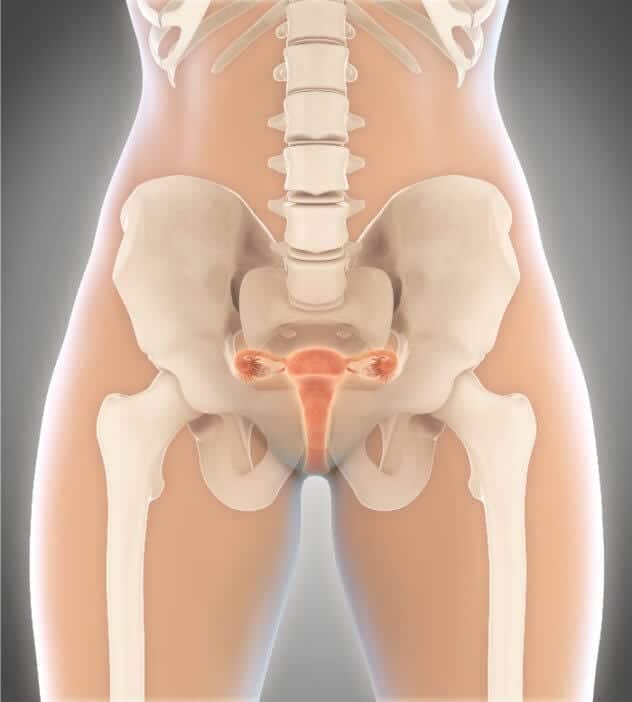

Die Ramzi Theorie besagt, dass man das Geschlecht eines Babys schon sechs Wochen nach der Empfängnis sicher vorhersagen kann. Dazu muss man lediglich die Lage der Plazenta betrachten: liegt diese auf der linken Seite des Uterus wird es ein Mädchen, liegt sie rechts, dann wird es ein Junge.